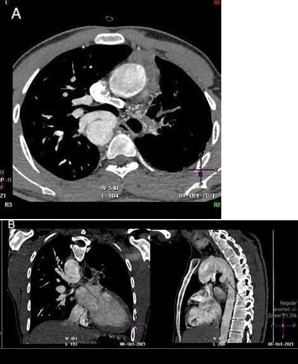

CT angiogram of chest shows complex cardiac disease including right-sided aortic arch (Figure 1), ventricular septal defect and overriding aorta (Figure 2). Non-visualization of the pulmonary trunk (Figure 3).

Two arterial supplies to the right lung arising from the descending aorta. A dominant one arising from the medial side that supplies the right upper lobe (Figure 3). Another smaller branch supplies the right middle and lower lobes (Figure 4).

Small blind-ended artery arising from the aortic arch at the take-off point of the left brachiocephalic artery (Figure 5) with non-visualization of left main pulmonary artery (Figure 3A). Multiple small arterial collaterals at the left hilum supplying the relatively hypo-plastic left lung (Figure 3A).

Figure 3: Contrast-enhanced CT chest axial (A), sagittal and coronal (B) views, showing an arterial supply to the right upper lobe arising from the descending aorta. Also there is an absent left pulmonary artery with multiple small collaterals at the left hilar region. Relative hypo-plastic left lung.